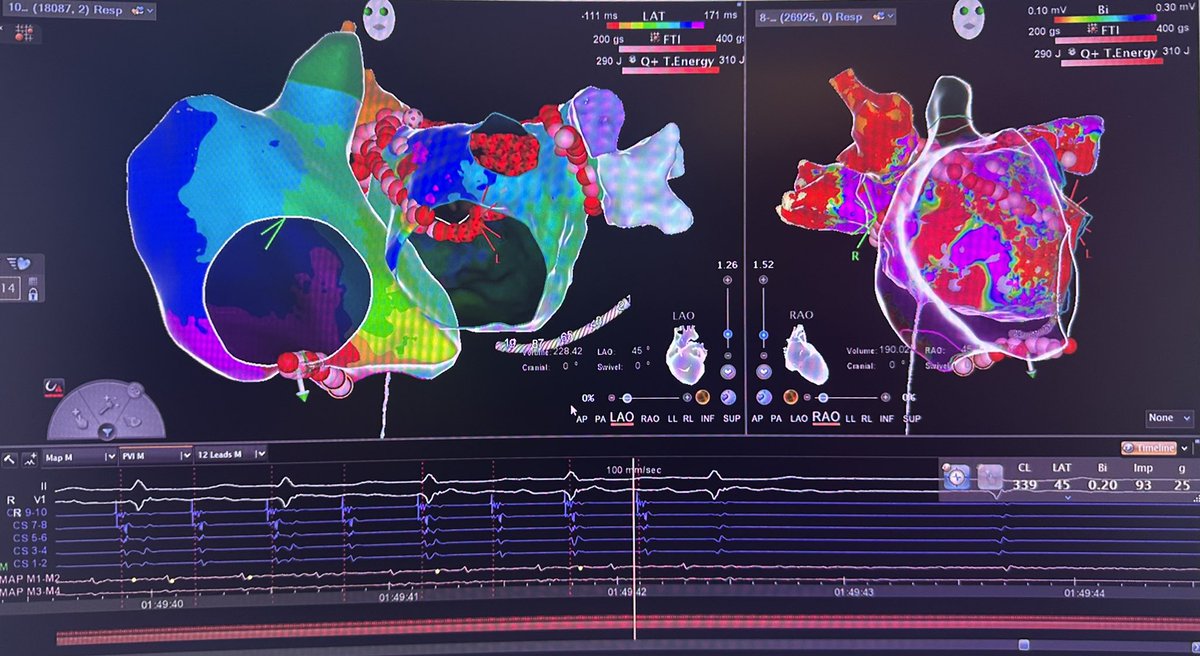

Nuvision Nav catheter @JNJMedTech, first case in New Jersey @RutgersNJMS, @UnivHospNewark in a concomitamment PFA and WATCHMAN procedure, great images and streamline.

English